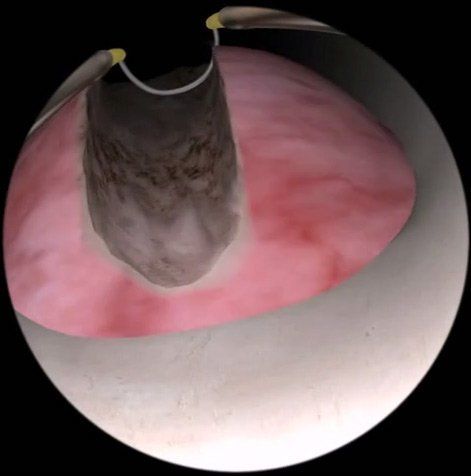

良性攝護腺增大

什麼是攝護腺良性增大?

隨著男性年齡增長,前列腺會增大。由於前列腺包圍尿道(連接膀胱的水管),這可能導致排尿困難、頻繁上廁所、排尿時用力、夜間起床排尿以及尿流不暢等症狀。這些症狀統稱為「下泌尿道症狀」(LUTS)。